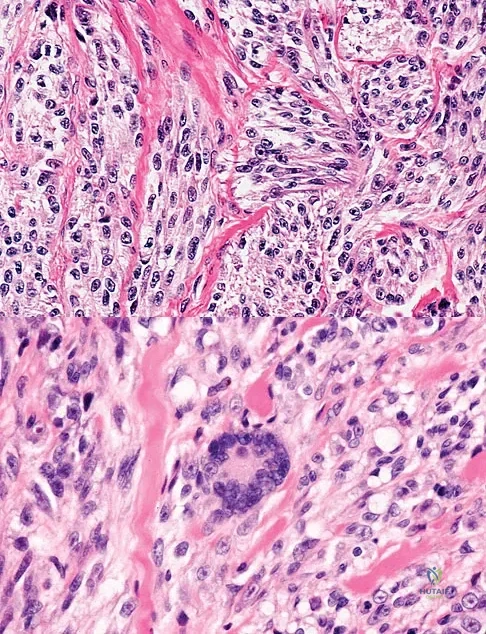

A 37-year-old man pulled his hamstring playing softball 3 weeks ago. The patient had not noted any mass prior to his injury. MRI scans of the posterior thigh are shown in Figures 4a and 4b. Figure 4c shows the biopsy specimen from a needle biopsy. What is the most likely diagnosis?

Malignant fibrous histiocytoma (MFH) is the most common soft-tissue sarcoma. MFH typically presents as a large mass, deep to the fascia with heterogeneous signal on MRI. The MRI scans show a heterogeneous lesion in the posterior thigh. There is significant high signal uptake on the T2-weighted image. The histology shows malignant histiocytic cells with marked atypia and pleomorphism. Histology of a hematoma would show only old hemorrhage and some granulation tissue. Lipoma and liposarcoma are both seen as a fat-containing lesion on histology. No significant fat tissue is seen in this histologic specimen. Histology of myositis ossificans would show bone formation. Simon SR (ed): Orthopaedic Basic Science. Rosemont, IL, American Academy of Orthopaedic Surgeons, 1994, pp 219-276.